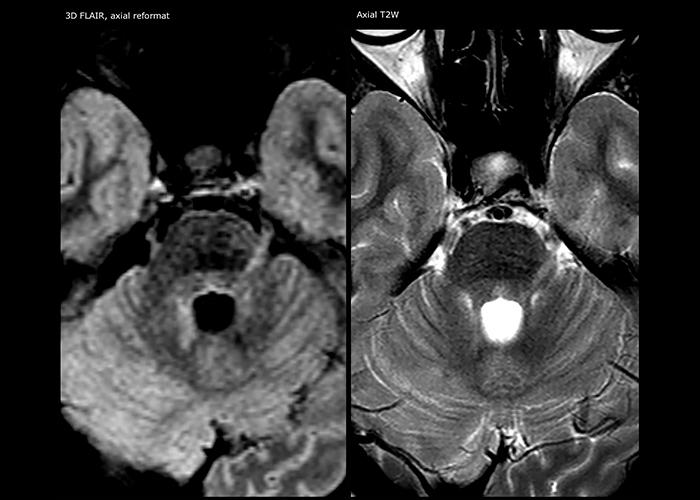

For MS imaging in the brain, Dr. Savatovsky uses 3D FLAIR as the basic sequence to visualize the lesions and assess the situation and lesion load. “We count the lesions in each location to determine if the criteria of the disease are fulfilled. We use a T2-weighted sequence because our neurologists are used to it. We compare the lesion load on FLAIR with a 3D T1 post-contrast sequence to help us determine whether lesions are old or new. We typically administer the contrast before the patient enters the machine because it shortens the examination time and allows to visualize active lesions that tend to be more visible after several minutes. When a differential diagnosis is difficult, we add sequences such as susceptibility imaging, because some focal MS lesions have a small vein in the center[3].”

“For MS imaging in the spine, the basic examination includes a sagittal T2 and a post-contrast sagittal T1-weighted sequence in the whole spine. These are done in two stacks and using thin slices, for example 2 mm, without gap. As in the brain, the T2-weighted sequence visualizes the overall lesion load and helps determine if lesions are old or new. The post-contrast T1- weighted sequence helps in assessing if a lesion is new. We will sometimes add a T1 inversion recovery sequence, which has very good sensitivity, if we don’t find any lesions on T2,” Dr. Savatovsky says. “Additionally, if there is contrast enhancement outside the spine, it’s usually not MS but another kind of inflammation.”